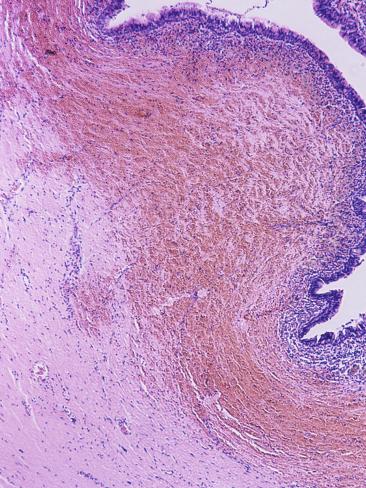

427 Resident And Fellow Education Feature

Bartholin gland cysts, although also located within the superficial tion of a Bartholin gland cyst (bartholinitis) is relatively common and may lead to pain, although Bartholin gland cysts also may be asymptomatic spect the images carefully for evidence of complications such as stone ... Fetch Content